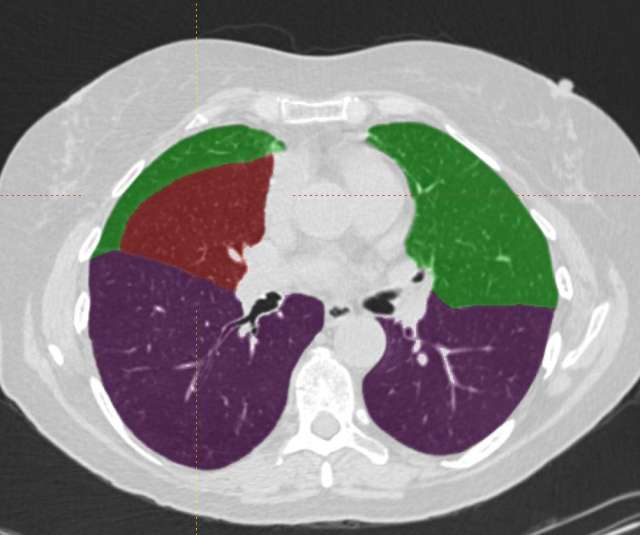

• Lobar Volumetrics

Lobar Segmentation